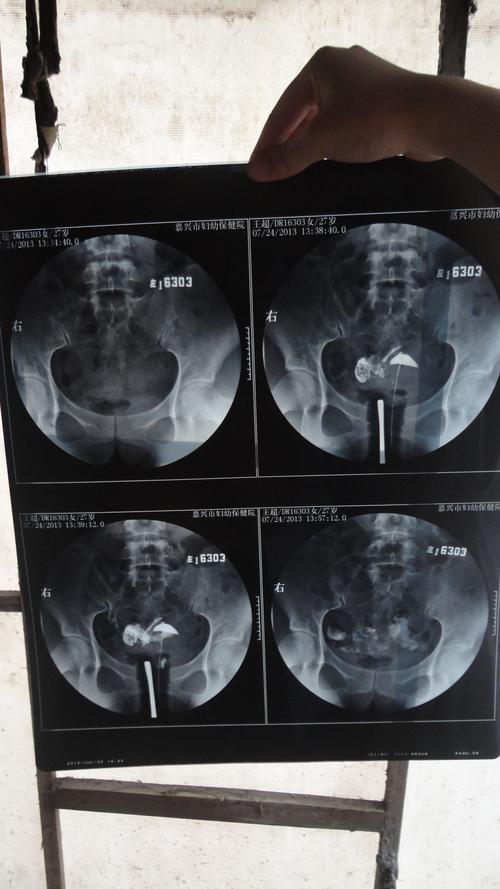

做输卵管造影之前,首先要进行妇科检查,需要做盆腔、阴道、宫颈的B超,然后才能判断是否具备孕卵和受精卵的发育阶段。通常在性生活后需要进行翻切,因为造影是非常安全的,但是由于输卵管造影需要进行开腹检查,所以如果不是十分的活跃,一般情况下在B超显示的时候就会比较清楚,无需进行开腹检查。

医生会在患者图像图像图像中对女性朋友的盆腔内的输卵管进行检查,然后就会根据检查情况,使用不同的仪器设备对女性的生殖系统进行检查,所以造影检查是不会对女性朋友产生影响的,只不过要注意,在做完输卵管造影之后,要进行一个月的休息,然后过几天就可以进行备孕,因为备孕的话,对胎儿的发育也是会有影响的。